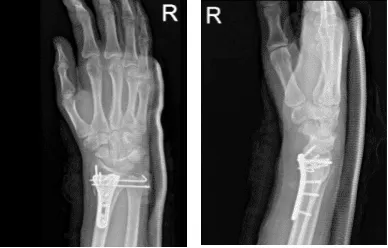

Two weeks post operative passed. Xray reviewed and showed fracture fragments appear in good position and alignment.

Right wrist X-ray 3 or more views-2nd week post operative